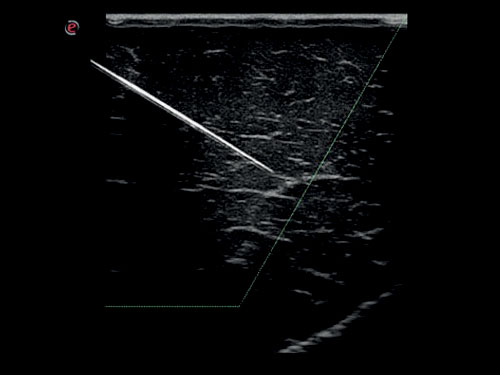

Viditelnost jehly: Vylepšená a jasná vizualizace jehly během zákroků.